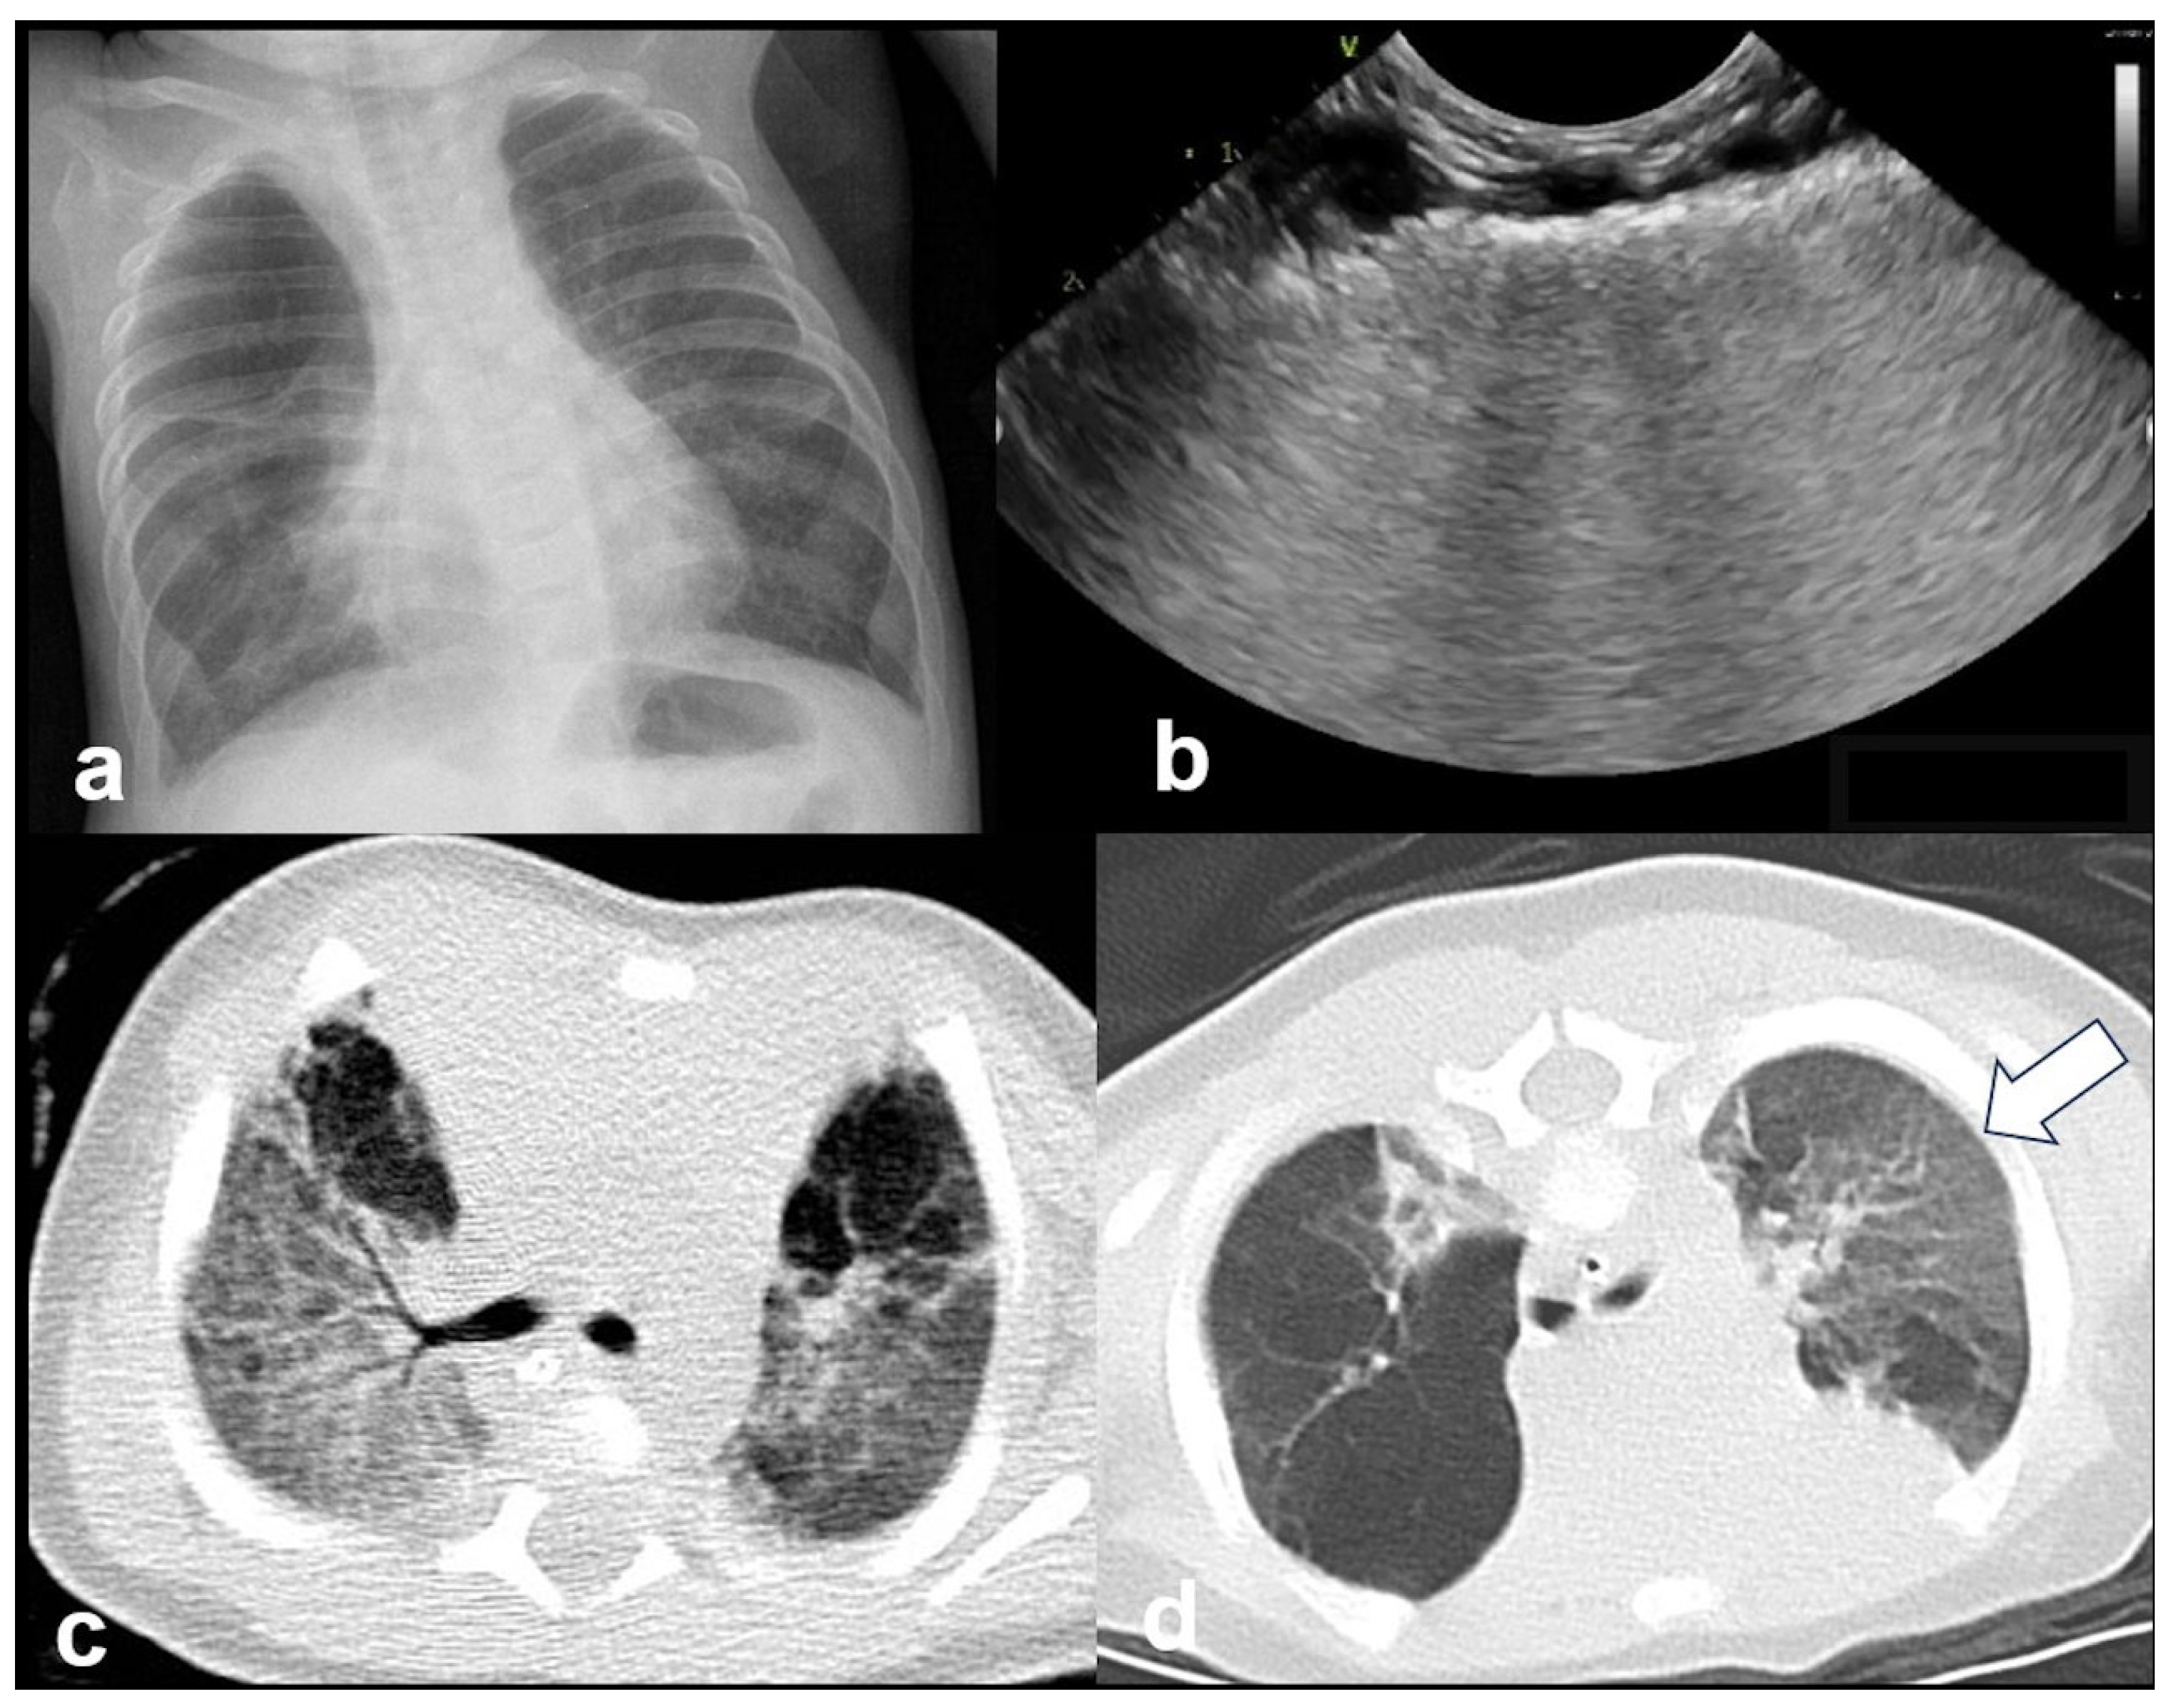

In RDS, lung ultrasound findings include consolidation or bilateral “white lung”, aero bronchograms, pleural line abnormalities, and the absence of A-lines (Figure 12, Figure 13, Figure 14 and Figure 15) [30,35,40,41].

Figure 12.

A frequent and characteristic imaging finding in RDS is the presence of B-Lines, bilaterally and throughout the lung parenchyma, in this case bilateral B-lines with no normal parenchyma (a) (absence of A-lines). Also, note the abnormal thickening ((a,b) arrows) of the pleural line (b). The overall sense is that of white lung.

Figure 13.

Normal to mild RDS: by chest X-ray (a); by LUS (b).

Figure 14.

Severe RDS shown on chest X-ray (a); LUS (b). The ability of the LUS to characterize the severity of the RDS is debatable.

Figure 15.

Severe RDS with sub-segmental(-pleural) consolidations. by LUS.

In RDS, specific LUS patterns describing lung aeration accurately predict the need for surfactant administration [35].

RDS is a common cause of neonatal respiratory failure, particularly in preterm infants, resulting from surfactant deficiency and alveolar collapse. LUS has become a valuable diagnostic tool for RDS, offering real-time visualization of lung pathology at the bedside [38,42,43,44,45]. A hallmark sonographic feature of RDS is the presence of dense, confluent B-lines throughout the lung fields, producing a “white lung” appearance due to the loss of normal aeration. Notably, the whole lung is typically involved, with a diffuse, bilateral distribution that distinguishes RDS from more localized pulmonary conditions [37,46,47]. Additionally, interspersed consolidations may be present, including hypoechoic and subpleural areas of alveolar collapse, reflecting regions of complete de-aeration. These consolidations often lack air bronchograms and are associated with irregular or thickened pleural lines. The combination of diffuse B-line patterns, global lung involvement, and patchy consolidations provides a highly suggestive ultrasound profile of RDS and facilitates early diagnosis. In addition, for RDS, LUS may be used for severity assessment and the monitoring of treatment response in the neonatal intensive care setting [16,20,27,29]. The ability of the LUS to characterize the severity of the RDS is debatable (Figure 14 and Figure 16) [48].

Figure 16.

Interstitial emphysema shown on chest x-ray (a) and LUS (b). This case underlines the superiority of CXR in differentiating this pathology from RDS, which has a similar LUS appearance.